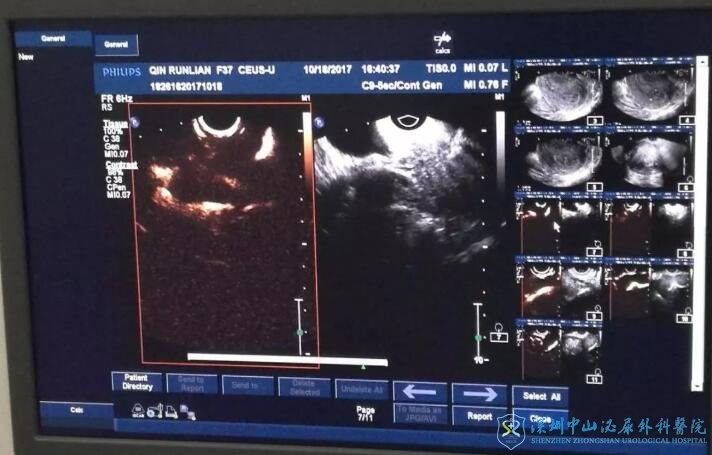

超声检查

B超发现卵巢旁长条状液性暗区,但是超声只能提示有液性暗区而不能最终确诊是否有积水,有经验的超声医生可以较准确判定。